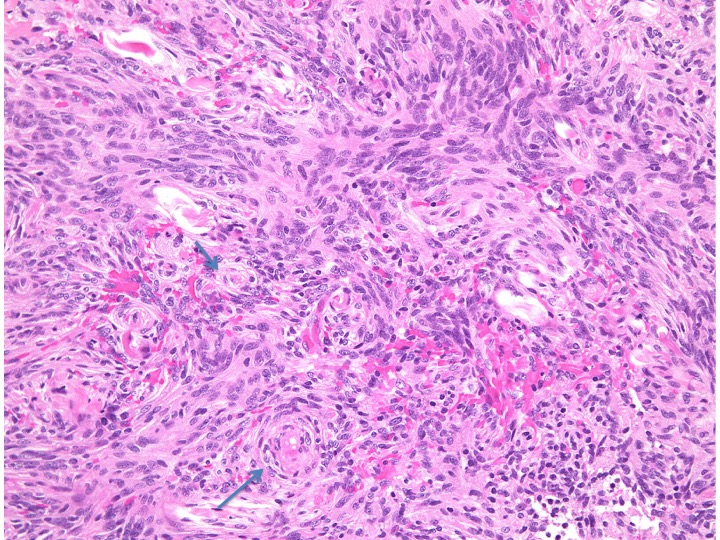

紡錘形細胞が放射状に配列する所見でstoriform patten (花むしろ)、またはcartwheel (車輪)状に似た様子が見られます。軟部腫瘍であるfibrous histiocytomaで良く見られるものです。本例ではCP-angle meningiomaに見られた所見で、fibrous meningiomaの診断です。MIB-1 indexはやや高く8%でしたが、壊死や異型性は見られず、Grade 1相当とみなされます。HE x200

Fibrous meningiomaですが、渦巻状(whorl, long arrow) patternや玉ねぎ茎状 (onion bulb, short arrow) patternなどが見られます。HE x200